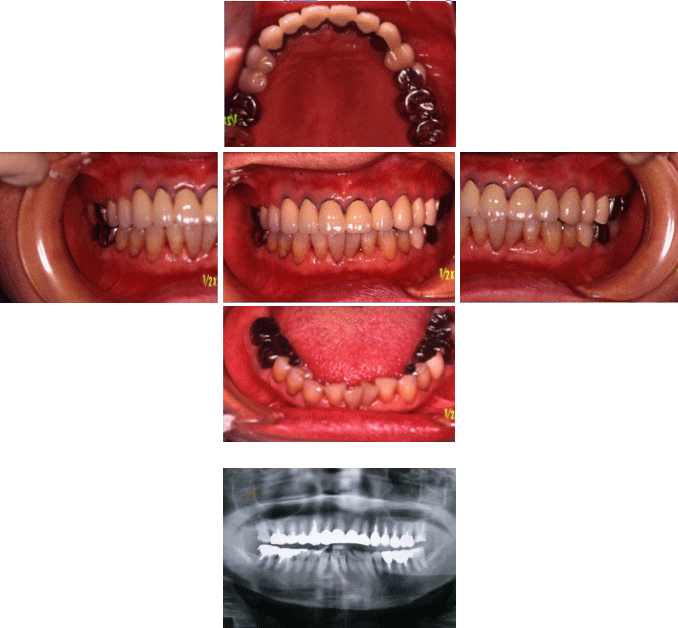

現在、85歳で全て自分の歯があります(28本)

もともと歯は強くなく、過去に神経や歯の根まで進んでしまった治療済のむし歯が17本もあります。

更に、歯周病により歯を支えている骨も無くなりかけています。

しかし、メンテナンスを根気よく続ける事で、途中むし歯・歯周病の再発はありましたが、1本の歯も失う事なく、現在も定期的に来院しています。